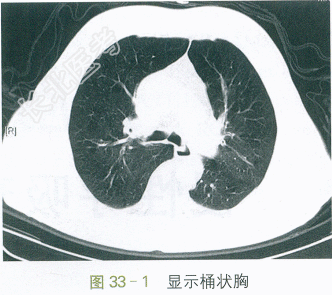

T37.2℃,P110次/min,R25次/min,BP145mmHg/88mmHg,神志清,神萎,呼吸急促,口唇发绀,球结膜水肿,颈软,颈静脉充盈,气管居中,桶状胸,双肺叩诊清音,听诊呼吸音粗,呼气相延长,两肺可及哮鸣音,未及湿啰音。HR110次/min,律齐,可及早搏。双下肢轻度凹陷性水肿。神经系统体征(-)。

胸部平扫CT:肺气肿,两肺少量慢性为主炎症。如图33-1、图33-2所示。